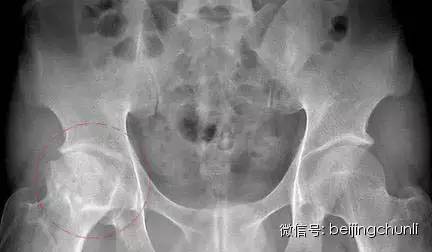

1股骨头坏死的 X 线表现

初期:髋关节间隙轻度增宽,以关节中下为主,主要因关节软骨增宽,股骨头外移所致,早期股骨头在外移2mm以内,晚期可达5mm,一般认为是关节旁及关节内软组织充血所致,可以逆转。

中期:股骨头皮质可以断裂形(台阶状)成角,基底处出现平行的双皮质征(双边征),其中台阶征及双边征是X线判断股骨头塌陷的早期征象,随后股骨头广泛脱位和碎解,其内可见死骨、裂隙、硬化和透光区,股骨头压缩变扁平,轮廓不规则,关节腔最初因股骨头变扁而增宽。股骨颈下方出现皮质增厚或骨膜增生,关节间隙可呈不规则变窄,髋臼关节面增生硬化,Sheaton线不连续,股骨头碎块可成为关节游离体。

股骨头坏死

上图为中期可能大

晚期: 股骨头骨结构完全消失,股骨头明显变扁或覃状变形,内有弥漫或局限性硬化或囊变区,关节间隙变窄,股骨头增粗,可有关节半脱位。髋臼缘和股骨头基底部增生变成骨赘,髋臼关节面出现硬化并囊变,股骨头与髋臼变扁,股骨颈吸收,使下肢变短。

上图为晚期可能大